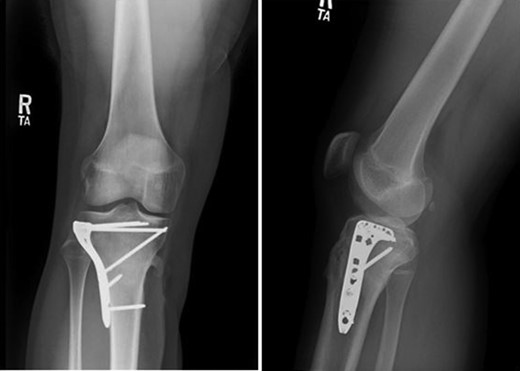

Patient is a 14-year-old male who slipped and fell while jumping off of a diving board and landed onto a flexed right knee. The patient was stable on presentation and neurovascularly intact with the knee locked in flexion. Skin was tenting anteriorly over the tibial tubercle and his compartments were swollen but compressible. A single plain film view (Fig. 1) was obtained prior to orthopaedic consultation. Closed reduction under sedation and splitting was attempted in the ED with partial but unsatisfactory improvement. Post-reduction radiographs (Fig. 2) demonstrated a tibial tubercle fracture with extension through the entire proximal tibial physis with metaphyseal involvement posteromedially. We classified this as a type IV tibial tubercle fracture, Salter–Harris II variant. In conjunction with patient and family we planned for urgent closed versus open reduction and application of knee-spanning external fixator. Immediately prior to surgery in the pre-operative holding area, the patient noted increasing right leg pain. In the operating room (OR), a marked increase in swelling with tense skin was observed. Due to rapidly progressive swelling and nature of the fracture, the decision was made to proceed with a 4-compartment fasciotomy of the right leg. The medial-sided fasciotomy (Fig. 3) revealed significant bulging of the superficial and deep compartments; however, the anterior and lateral compartments were less swollen. The fracture was unable to be closed reduced intraoperatively, therefore proximal extension of the medial fasciotomy wound was performed to open and reduce the fracture under direct visualization. Anatomic reduction was achieved and a knee-spanning external fixator was applied (Fig. 4). Approximately 72 hours later the patient was brought back to the OR for irrigation and debridement, lateral wound closure, and medial wound vacuum placement. Another 72 hours later, he returned to the OR for removal of the external fixator, ORIF, and split-thickness skin grafting of the medial fasciotomy site. An anterolateral approach was used with a 3.5 mm proximal tibial locking plate (Fig. 5). At most recent follow-up (Fig. 6), six months post-op, the patient is pain free, ambulating without assistive device, and has returned to all desired activities.

AP and lateral intraoperative fluoroscopic images following ORIF with proximal tibial locking plate.